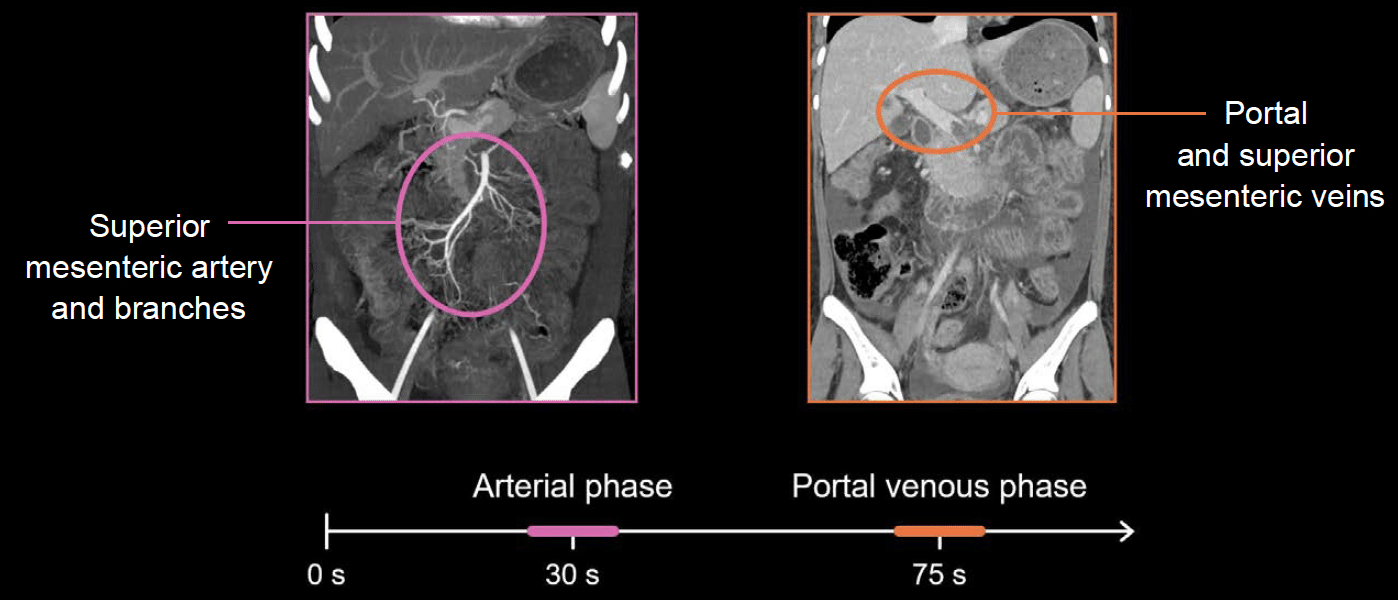

Abdominal CT Phases LITFL Radiology Library

Abdominal CT Phases LITFL Radiology Library

Abdominal CT Phases LITFL Radiology Library

Abdominal CT Phases LITFL Radiology Library